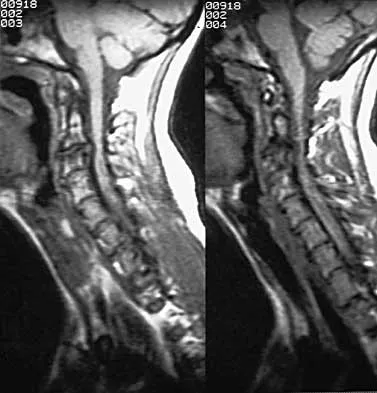

A 23-year-old man sustains a unilateral jumped facet with an isolated cervical root injury in a motor vehicle accident. Acute reduction results in some initial improvement of his motor weakness. Over the next 48 hours, examination reveals ipsilateral loss of pain and temperature sensation in his face, limbs, and trunk, as well as nystagmus, tinnitus, and diplopia. What is the most likely etiology for these changes?

Explanation